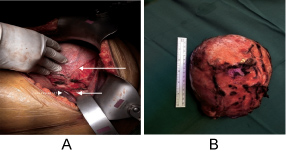

Laboratory work-up including full blood count, blood chemistry, serum electrolytes, liver function tests, cortisol, aldosterone, normetanephrines, total metanephrines, and urine metanephrines were all within normal ranges. Imaging showed a large right adrenal mass measuring 16 by 11 cm detected through CT and MRI of the abdomen (Figure 1a and Figure 1b). Despite negative biochemical and radiological findings, pre-operative probability of pheochromocytoma was thought to be high given the persistently elevated blood pressure. Therefore, the patient was started empirically on prazosin and later addition of propranolol.

Figure 1: Axial and coronal sections of MRI abdomen showed the hetrogenous mass in the right adrenal gland. View Figure 1

MRI abdomen (Figure 1a and Figure 1b) showed a large right suprarenal mass measuring 16 × 8 × 11 cm. It demonstrated heterogenous predominantly bright T2 signal intensity and heterogenous slight T1 low signal intensity. The mass is displacing the surrounding organs and structures with no definite regional invasion. Malignant features are not clearly demonstrated. Primary vs. metastatic adrenal tumor vs hemorrhagic mass cannot be differentiated. Multiple lymph nodes are noted in the right renal fossa measuring approximately up to 1.1 cm. The visualized abdominal organs were otherwise unremarkable. No other special MRI techniques were used.